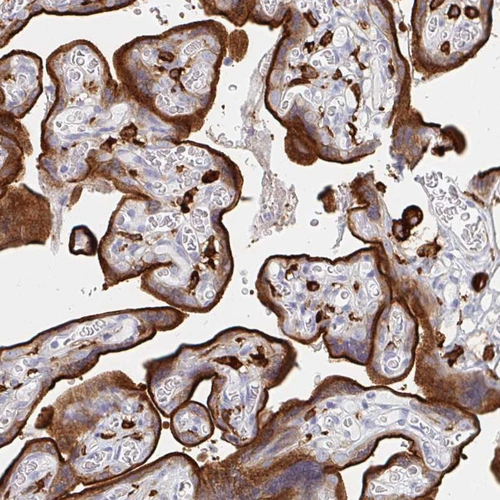

Immunohistochemistry analysis in human placenta and skeletal muscle tissues using HPA028888 antibody. Corresponding DAB2 RNA-seq data are presented for the same tissues.